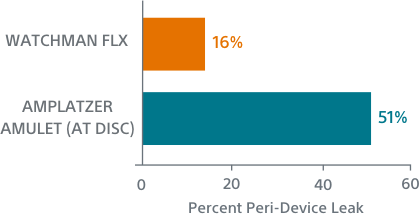

WATCHMAN FLX Demonstrated Statistically Superior Complete Occlusion** vs Amulet (p=0.001)

**Complete LAA occlusion defined as no visible peri-device leak (PDL) and absence of contrast patency in the distal LAA (LAA/left atrium Hounsfield ratio <0.25)

Simplified Assessment

AMPLATZER AMULET1

Hidden Leaks